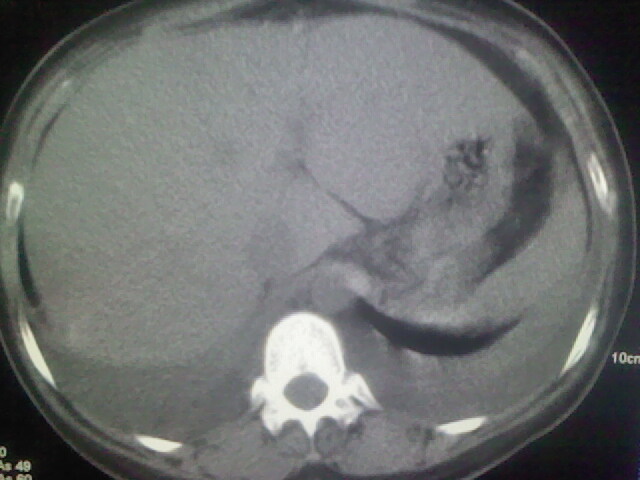

女,24,剖腹产后,突觉胸痛,干咳,不能平卧

双侧胸腔积液,肺泡性肺水肿。后纵隔好像有占位。

考虑肺梗塞、肺水肿,双侧胸腔积液

肝脾大,双侧胸腔积液,双肺水肿,肺动脉[包括远端小动脉],左右心房,左心室增宽,右心室主动脉无明显改变,符合左心功能不全征;;建议除外二尖瓣关闭不全,扩张性心肌病

急性心衰可能,肺梗塞??我没看到病变的具体位置,楼上的给讲讲啊

临床资料及影象表现支持围产期扩张型心肌病改变,心衰。

考虑产后心肌病,心功能不全,肺水肿,双侧胸腔积液。